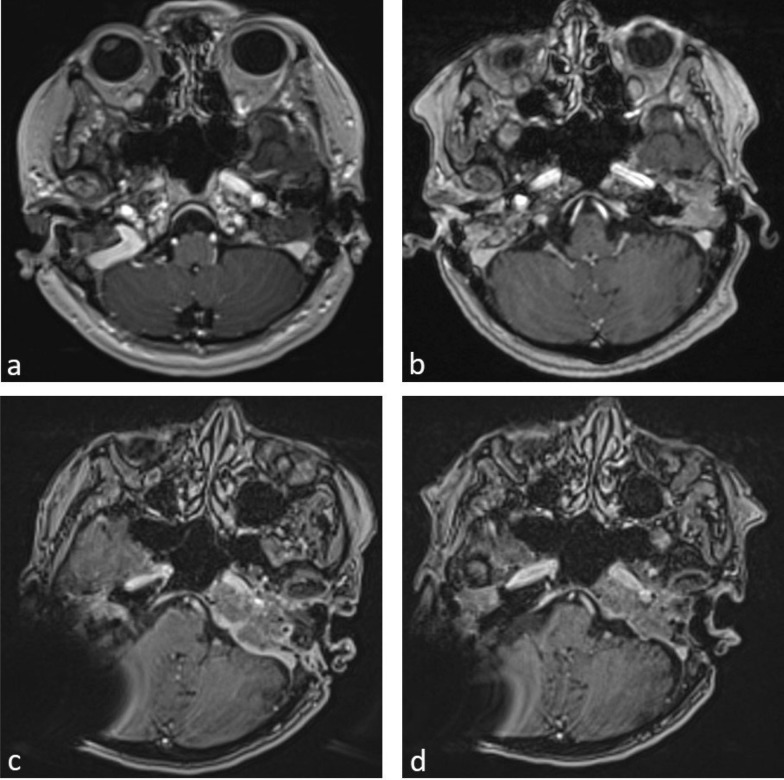

Case presentation: We report on a 58-year-old female patient who presented to our clinic for the first time in 2014 with a bilateral skull base osteomyelitis. The patient had a history of several comorbidities, including hypogammaglobulinemia following the successful treatment of a relapsed B-CLL. Different surgical treatments had already been attempted at the time of initial presentation. Several rheumatological, orthopedic, haemato-oncological and divergent microbiological differential diagnoses could be ruled out. Despite various interdisciplinary treatment attempts (including surgery, antibiotic therapies and hyperbaric oxygen therapy) the progress led to a palsy of the caudal cranial nerve group in 2022. With all preceded microbiological sampling being negative, we initiated species specific PCRs covering atypical organisms. An atypical infection of Mycoplasma pneumoniae was detected. After starting antibiotic therapy with azithromycin and doxycycline the progress could be halted and the palsies were regredient. The following MRI scans confirmed a decline in findings.